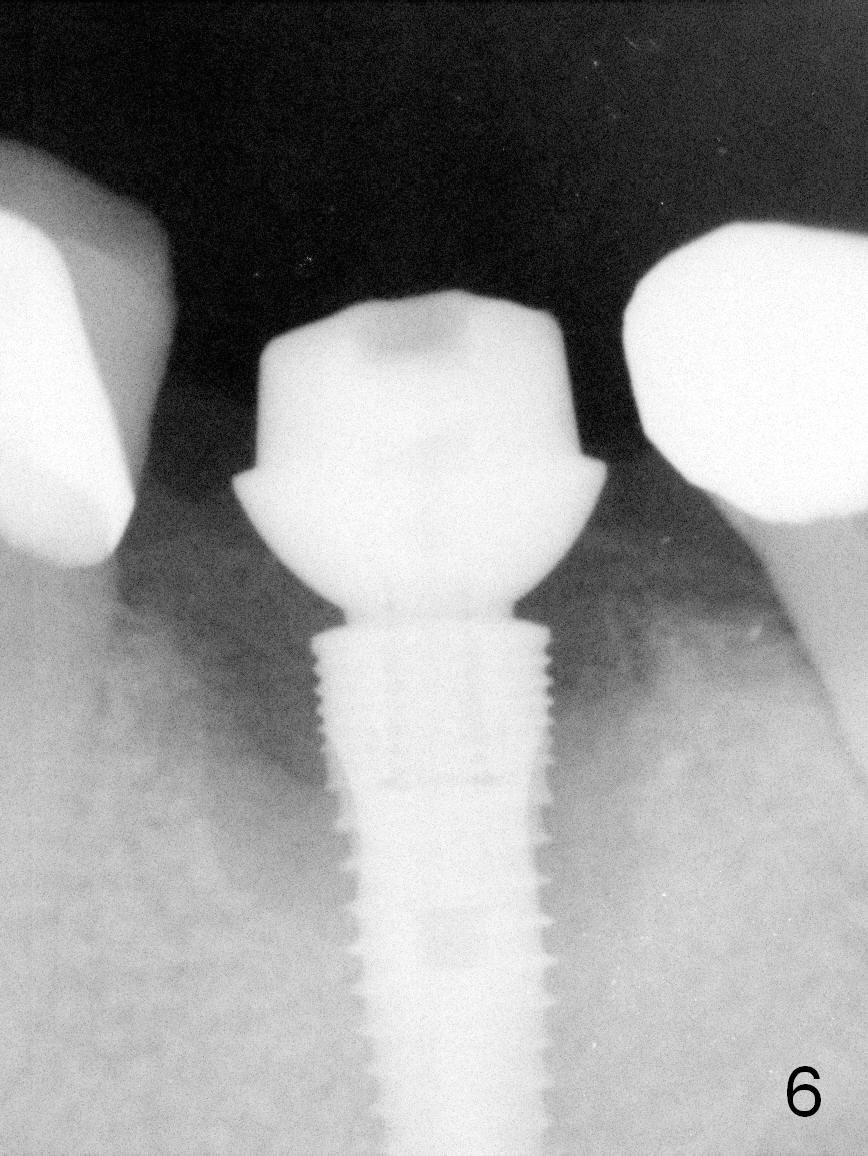

As expected, the lingual margin of the abutment is supragingival 2 months postop. The immediate provisional is fractured (Fig.6). The abutment is changed to 5.8x4(2) mm and impression is taken.